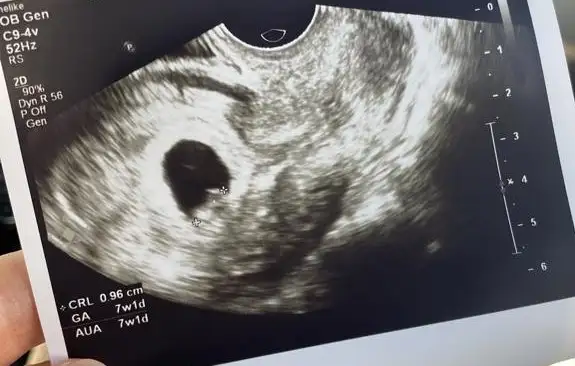

Merhaba, bizim kese görüntülerimiz hafta hafta bu şekilde şu an 7+1 deyiz, yorumlara bakınca kafam karıştı ne olabilir acaba? :)))

• WhatsApp Image 2023-06-21 at 16.12.56.webp

WhatsApp Image 2023-06-21 at 16.12.56.webp

14,3 KB · Görüntüleme: 480